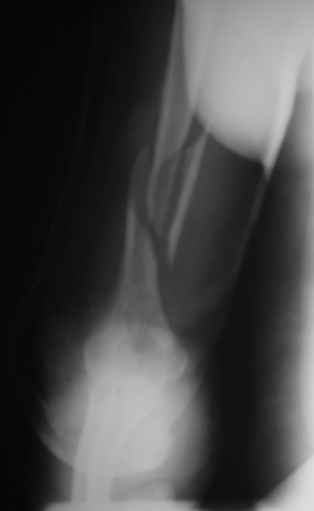

Теперь непосредственно по больному. Лечим функциональной повязкой, добились вот чего (приложение). Будем признательны за дальнейший комментарий - мое мнение, что можно продолжить без операции.

Имя     : Праздничная репозиция.JPG

Имя     : Прямой.JPG